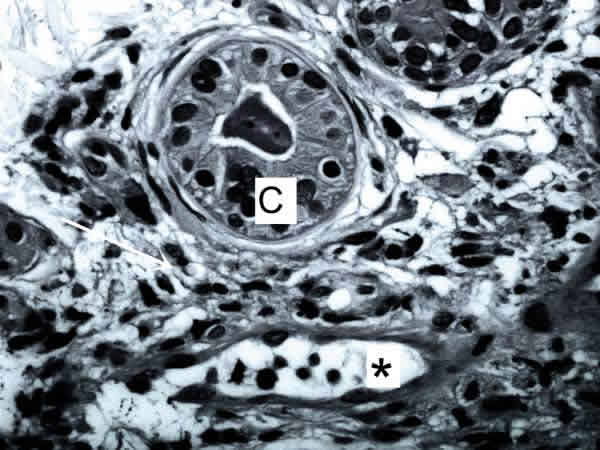

Fig. 1: La unidad capilar*-MEC —> –célula(C) es la unidad mínima de vida. Ofrece el soporte estructural de tensegridad al tejido, una matriz a través de la cual se transmite el estímulo de la inervación, una red capilar para la nutrición y desecho de detritus de las células parenquimatosas, el marco de vigilancia y acción del sistema inmune, una red de flujo energético y una autopista de información local y a distancia.